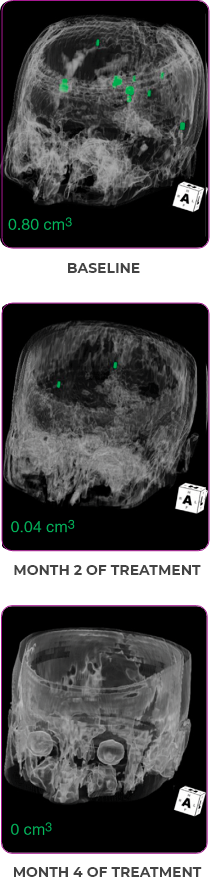

MRIa imagery of the brain. Green voxels indicate decreased burden of metastatic disease; further quantified by accompanying measurement in green.1

Response in primary and metastatic lesions1

SCAN 3: BRAIN

aMRI, magnetic resonance imaging.

Pre- and post-treatment imaging, by Rosen EY et al, is licensed under Creative Commons License CC BY 4.0.